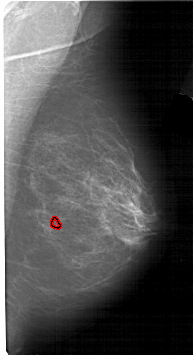

A_1487_1.RIGHT_MLO

FILE: A_1487_1.RIGHT_MLO.OVERLAY

TOTAL_ABNORMALITIES 1

ABNORMALITY 1

LESION_TYPE CALCIFICATION TYPE PLEOMORPHIC DISTRIBUTION CLUSTERED

ASSESSMENT 4

SUBTLETY 1

PATHOLOGY MALIGNANT

TOTAL_OUTLINES 1

BOUNDARY